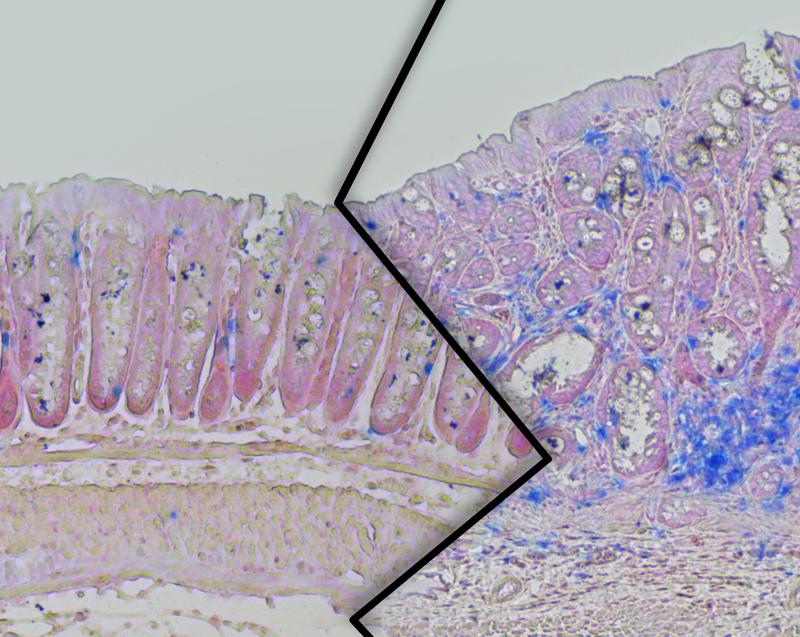

Dickdarmgewebe aus schlanken (links) und übergewichtigen (rechts) Mäusen der Studie. Bei den übergewichtigen Tieren ist ein verstärktes Tumorwachstum mit erhöhter Immunzellanzahl (blau) zu sehen.

Bild: Max-Planck-Institut für Stoffwechselforschung, Köln